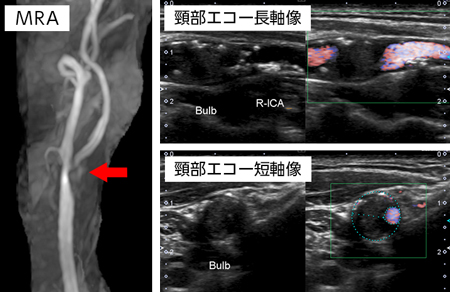

60代男性、右内頸動脈狭窄症

健康診断にて右内頸動脈狭窄症を指摘されて来院。

MRAにて右総頸動脈から内頸動脈に高度狭窄を認める(矢印)。

頸部エコーにて血管内腔の狭窄を認める。カラー部分が血液が流れている。